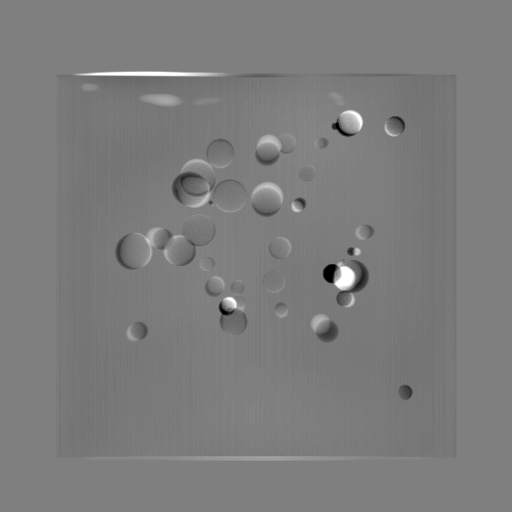

Refer to caption

(a) Orthogonal 0superscript00^{\circ}

(b) Perspective 0superscript00^{\circ}

(c) Perspective deformation ((b)-(a))

(d) Perspective 180superscript180180^{\circ}

(e) Difference of Perspective 0superscript00^{\circ} and 180superscript180180^{\circ}

(f) RGB 0superscript00^{\circ} and 180superscript180180^{\circ}

Figure 6: An example for perspective deformation learning from dual complementary views: (a) the orthogonal projection of the 3D bead phantom from the 0superscript00^{\circ} view; (b) the perspective projection from the 0superscript00^{\circ} view; (c) the difference image between (b) and (a); (d) the perspective projection from the 180superscript180180^{\circ} view; (e) the difference image between (d) and (b); (f) the RGB stack of the 0superscript00^{\circ} and 180superscript180180^{\circ} perspective projection images, where the magenta and green areas correspond to the positive (bright) and negative (dark) areas in (e). The intensity range [0, 11] is converted to [0, 255] for visualization.

Note that when and only when z=0𝑧0z=0, which is m=m=1superscript𝑚𝑚1m^{\prime}=m=1, d180subscript𝑑superscript180d_{180^{\circ}} and dPDsubscript𝑑PDd_{\text{PD}} both equal to 0. This provides a practical way to observe which structures suffer from perspective deformation by assessing deviations between the two complementary views.

The orthogonal and perspective projection images of the same 3D bead phantom in a complementary view setting are displayed in Fig. 6. Fig. 6(c) shows the perspective deformation, which is the difference between the perspective projection (Fig. 6(b)) and the orthogonal projection (Fig. 6(a)) from the 0superscript00^{\circ} view. Fig. 6(c) clearly demonstrates that the magnitude of perspective deformation increases from the center outwards radially. The 180superscript180180^{\circ} perspective projection image is displayed in Fig. 6(d) and its difference with respect to the 0superscript00^{\circ} perspective projection is displayed in Fig. 6(e). Fig. 6(e) is similar to Fig. 6(c) in bead areas, which illustrates that the deviation between two complementary views has strong correlation to perspective deformation. To integrate such dual-view information, like Fig. 5(d), we convert the perspective projections images from the 0superscript00^{\circ} and 180superscript180180^{\circ} views to a 3-channel RGB image in Fig. 6(f). The red and blue channels use images from the 0superscript00^{\circ} view, while the green channel uses images from the 180superscript180180^{\circ} view. In the RGB images, the color reveals the intensity difference between the 0superscript00^{\circ} and 180superscript180180^{\circ} perspective projection images. Grey areas contain close intensity values from both views. Instead, magenta and green areas indicate larger intensity values from the 0superscript00^{\circ} and 180superscript180180^{\circ} views respectively, where perspective deformation correction is necessary. They correspond to the positive (bright) and negative (dark) areas in the difference image in Fig. 6(e). In Fig. 6(f), the magenta beads and their corresponding green beads are located close to each other, which allows a network with limited receptive field size to capture bead-to-bead (point-to-point) dependency.